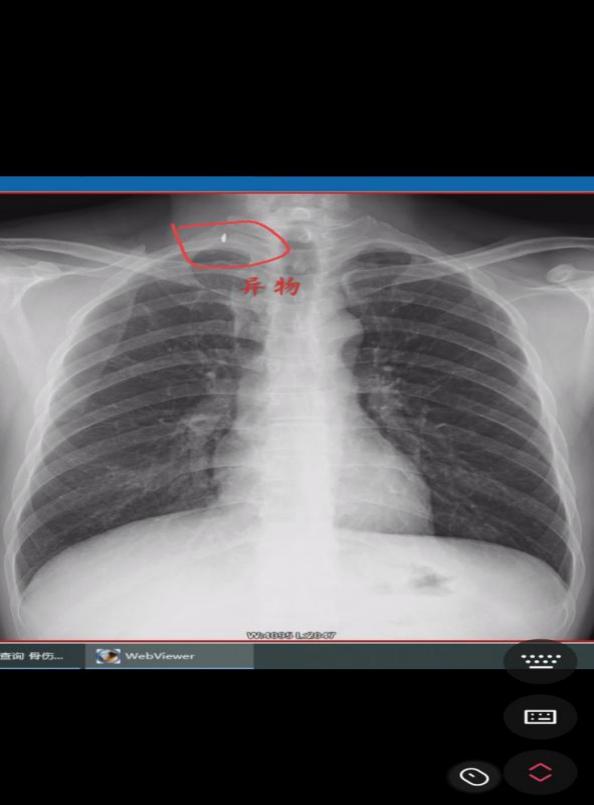

科室主任汪绪芳了解情况后,立即开辟绿色通道,安排医护全程陪诊,颈胸部X线片检查提示:患者右侧颈部局部异物留存,需要急诊手术取“弹片”。此时,距患者受伤已有1个小时,形势危急,肖劲齐立即与病人及家属沟通,详细讲解颈部血管、神经的复杂解剖结构,必须立即进行急诊手术,错过急诊手术时间可能会出现异物贯穿颈部大血管,大出血,造成生命危险。并立即向上级医师科副主任刘铀宁汇报患者病情及治疗方案,同时与科室主治医师刘安明一起做好手术准备,通知手术室开辟急诊通道。

(术前DR片) ????????????????(术后DR片)